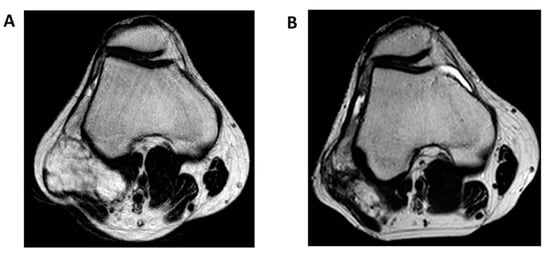

- Tateishi, U.; Hasegawa, T.; Nojima, T.; Takegami, T.; Arai, Y. MRI features of extraskeletal myxoid chondrosarcoma. Skelet. Radiol. 2006, 35, 27–33. [Google Scholar] [CrossRef] [PubMed]